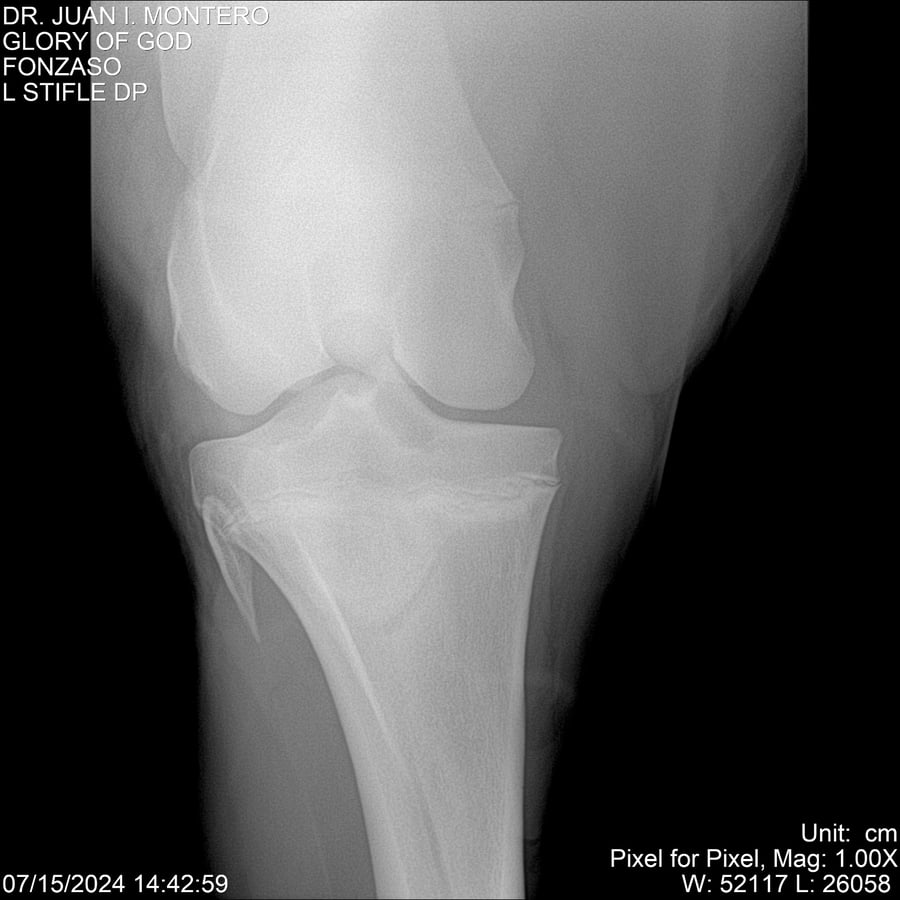

LOTE 10, GLORY OF GOD 🔥 🔥 🔥 Lote Anterior Volver al remate Lote Siguiente Ficha Contacto Montevideo - Ficha del Lote Identificador: #281389 Categoría: Yeguarizos Montevideo - 115 Visualizaciones ClicData Contacto Empresa: Abelenda N. R., Walter Hugo Nombre*: Teléfono* : E-mail* : Mensaje Enviar Registrese gratis Este contenido Exclusivo está disponible sólo para usuarios registrados Ingresar